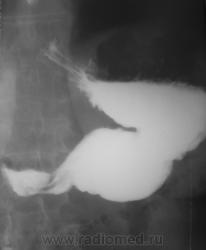

1. Аденоидные полипы в антральном отд. желудка.

Во всяком случае полиповидное выпячивание в антруме налицо, но думаю оно подслизистое... А варикоз - явно не виден, есть в кардии складка небольших размеров, но явно в глаза она не бросается, хотя складки везде толстоваты...

полиповидные образования в антральном отделе +грыжа ПОД

Смею предположить (с учетом наличия + тени кардии желудка по верхне-медиальной стенке, некоторого удлинения и выпрямления кардиального канала, неровности контуров) кардио-эзофагеальный рак без стеноза. В антруме - полипы. Вряд ли подслизистые образования, такие на вершине складок не образуются.

На снимке который поместил Анатолий Владимирович, м.б. или ГПОД (кардиальная) или ахалазия пищевода,при ней газовый пузырь отсутствует или уменьшен в размере. А м.б. и c-r пищеводно-желудочного перехода.

Наблюдение архивное. Я этот снимок привел как типичный пример ампулы пищевода, нормальной, в горизонтальном положении тела, которую наша братия, почти поголовно принимает за грыжу пищеводного отверстия, и соответственно с нашей подачи хирурги пытаются это оперировать...

1.о варикозе вен н\трети пищевода стоит подумать, весьма коварная вещь;

2. полипы препилорического отдела не вызывают сомнения, но что тут интересно - картинка то меняется, периодически крупный дефект выполнения как бы исчезает...но появляется в основании луковицы - сдается мне - это полип на длинной ножке, вот и гуляет он через привратник туда-сюда, вспоминайте - симптом "собачки на цепочке"...

Да, данные ФГДС подтвердили наличие полипов в препилорической части, один действительно - "гулящий" - на длинной ножке.